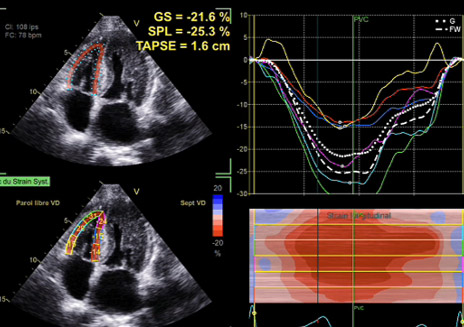

En échocardiographie, une augmentation d’épaisseur septale dès 12 mm doit alerter et faire pratiquer une étude Doppler tissulaire à l’anneau mitral et un strain global longitudinal avec recherche d’un aspect en cocarde (Figure 1) avec déformations à l’apex beaucoup moins pathologiques que les déformations à la base aux segments moyens.

Figure 1 : Amylose TTR héréditaire . 64 ans

Cet aspect est fréquent, évocateur mais pas pathognomonique du diagnostic ; de plus, si la coupe apicale est de mauvaise qualité, si le ventricule gauche est tronqué, il y aura un aspect en cocarde, mais uniquement parce que l’apex n’est pas dans l’image ! La rigueur des acquisitions des coupes apicales en échocardiographie transthoracique est donc fondamentale.

Il faut aussi étudier le ventricule droit, qui est souvent hypertrophié (comme le septum inter atrial et parfois les valves) et les oreillettes qui sont dilatées (mais pas extrêmement alors que leur fonction est souvent effondrée) (Figure 2).

- Évaluation du cœur droit (dilatation, strain, épaisseur paroi libre) et des oreillettes : une dysfonction ventriculaire droite (strain de la paroi libre < 17 %) est un critère pronostique péjoratif fort ;